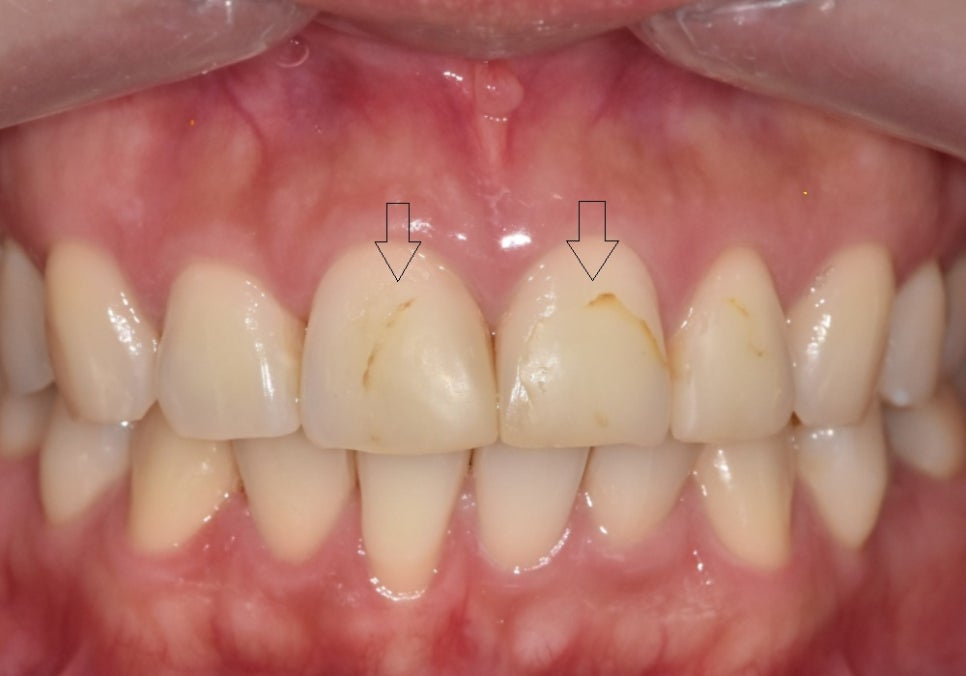

250503 고덕역 치과 반점치 얼룩덜룩한 치아, 치료 실패 줄이는 5가지 기준

서로 다른 치료를 적용했지만,

색상과 형태는

주변 치아와 자연스럽게 어울리도록

세밀하게 조율했습니다.

이 과정에서는

원내 기공소에서 기공사와 직접 소통하며

보철 제작을 진행했기 때문에,

미세한 색감이나 형태 조정도

즉각적으로 반영할 수 있었습니다.

그 결과,

서로 다른 재료를 사용했음에도

앞니 전체가 하나의 치아처럼

자연스럽게 이어질 수 있었습니다.